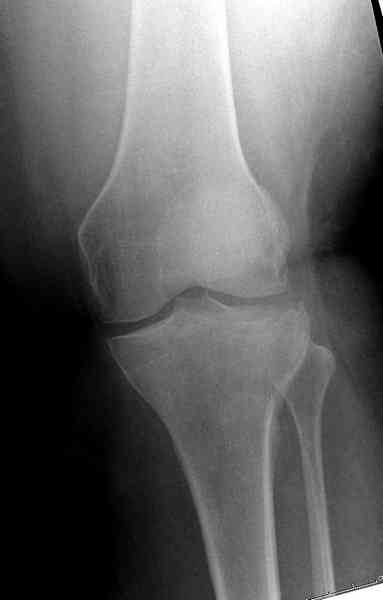

Из медиального окна можно приподнять латеральную

импрессию. Фиксация тремя параллельными шурупами в

эпифизарной части над импрессией. Создается крыша,

которая предупредит коллапс. На образовавшуюся полость - костная пластика из аутокости или синтетический заменитель. Мы применяем Osteoset в 4-5 мм диаметре таблеточки или иньекционную форму Prodens.